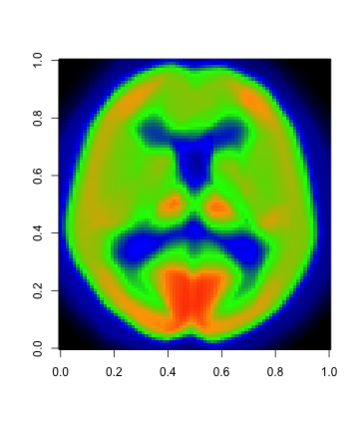

In this paper, we propose a robust estimator for the location function from multi-dimensional functional data. The proposed estimators are based on the deep neural networks with ReLU activation function. At the meanwhile, the estimators are less susceptible to outlying observations and model-misspecification. For any multi-dimensional functional data, we provide the uniform convergence rates for the proposed robust deep neural networks estimators. Simulation studies illustrate the competitive performance of the robust deep neural network estimators on regular data and their superior performance on data that contain anomalies. The proposed method is also applied to analyze 2D and 3D images of patients with Alzheimer's disease obtained from the Alzheimer Disease Neuroimaging Initiative database.